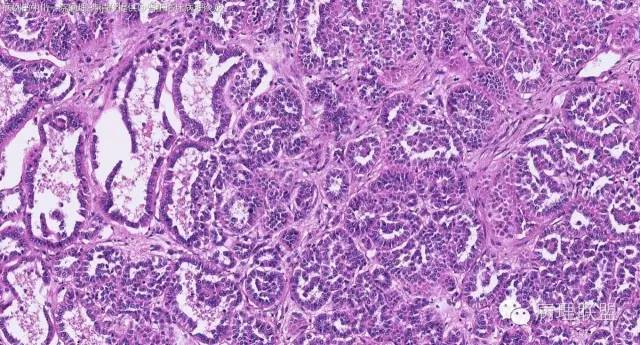

女性,50岁,肾上腺肿物(影像及手术均确认肿物位于肾上腺,界限清楚)。血压升高。(病例由 中山一院病理 曹清华提供,致谢!)

病例讨论

伴假腺样结构的肾上腺皮质腺瘤,合并髓脂肪瘤

从肿瘤的位置及镜下与肾上腺皮质的关系看,应该像是皮质来源肿瘤。假腺样结构的皮质腺瘤没有见过,似乎文献也还没查到。另外inhibina, melanA, syn均阴性(肿瘤旁正常皮质阳)感觉有点迷惑。。。请老师指教,有相关文献么?@武警嘉兴医院 周泉

假腺样是细胞粘附性差了导致。往往可以伴随黏液成分,组化上这几个抗体应该至少会有灶性阳性。

这个我再仔细看下。但,我们这例腺管结构不像是粘附差所致,是真的腺管;间质目前还没有看到有间质粘液变性区域;inhibina, syn, menlana是真的不阳,灶性都没有...